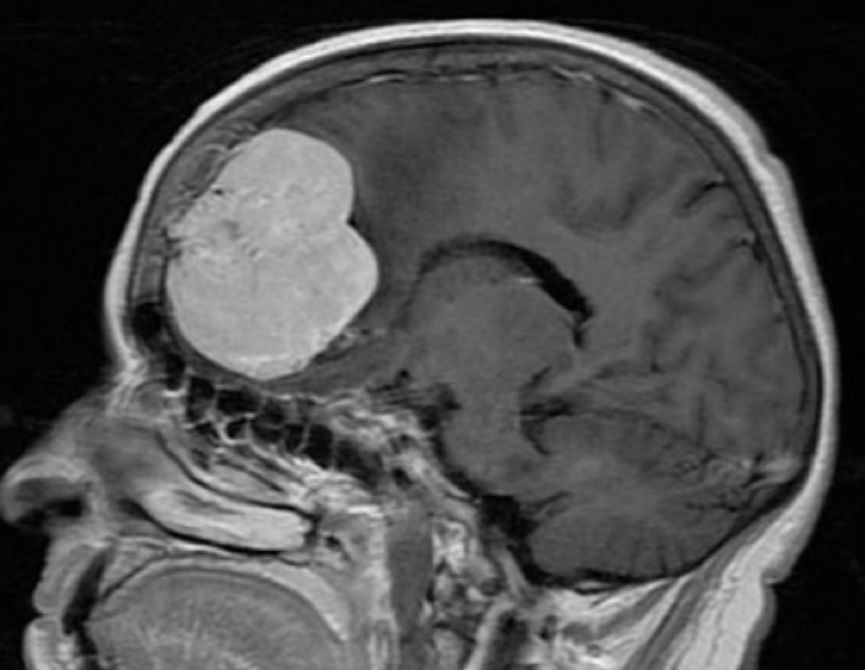

脑瘤有良恶性之分,恶性发展快,病程短,神经系统症状逐渐出现,并且进行性加重,带瘤存活 20 余年的可能性微乎其微。

脑胶质瘤

良性发展慢,病程长,患者可以没任何症状,也可以随着肿瘤生长,影响到脑部血液循环,阻塞脑脊液的循环通路,造成颅内积水或脑水肿,甚至会发生脑疝,危及生命。

虽然良性肿瘤存活期可能大于 20 年,但症状应进行性加重,不会以反复发作、不残留神经功能障碍为表现。

脑膜瘤